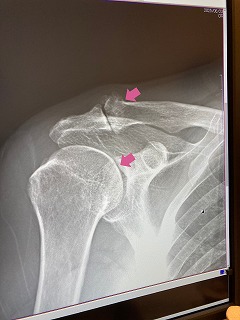

5月末、東HSYのパワーチュービーに巻かれて、右肩の亜脱臼、再び病院通い

その後、脱臼による痛みは8月末ごろ軽減、ストレッチ、筋トレ再開